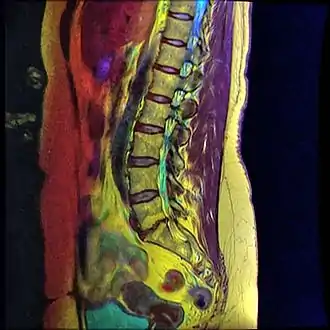

MRI shows retrolisthesis arrows ( and signal change at C3-C5 arrow heads)

Retrolisthesis of L5-S1